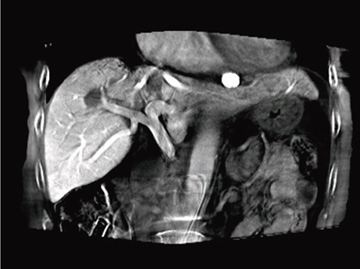

このロボットアームのユニークな回転撮影により,Cアーム装置による世界初の大口径でのC-arm Cone Beam CT(以下,C-arm CT)撮影を可能にした“Large Volume syngo DynaCT”(以下,LV DynaCT)も同時に発表された。この結果,従来のC-arm CTでは不可能であった肝臓のほぼ全域を撮影範囲とし,3次元画像の再構成が可能となった(図1)。

このLV DynaCTは,FIS(Flexible Isocenter System)により,コーンビーム中心から外れた点を回転中心に設定し,左右独立したオフセット回転撮影を実行,その後2つのオフセットデータを統合することにより,従来のDynaCT撮影範囲の2倍近い回転撮影視野を実現した(図2)。ただし,LV DynaCT撮影には,左右のオフセット回転撮影時間と,その左右移行時間という合計撮影時間の問題があった。オフセット回転撮影は,左右それぞれの体幹部を6秒間で220°の回転撮影を行い,左右オフセット回転撮影までの移行時間は4秒,合計16秒間の撮影が必要となる。